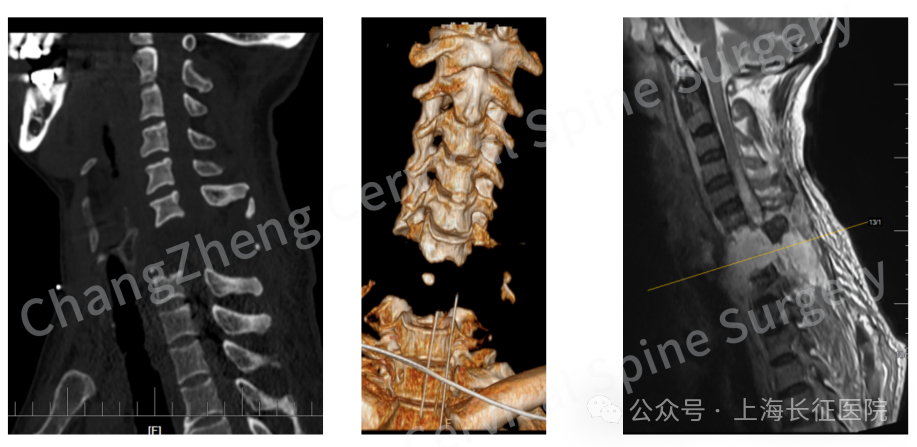

眼前这位患者,几乎已被宣判“死刑”。影像学检查显示,患者发生了罕见的大跨度颈椎离断式脱位,脊髓严重挫伤、关键的神经血管结构撕裂。

影像检查显示患者颈椎罕见大跨度脱落

“身首离断”,手术难度堪比登天

当时,患者因颈部遭受机械臂重击,导致颈椎瞬间遭受毁灭性损伤,当场高位截瘫、心跳骤停,经紧急心肺复苏才勉强恢复微弱生命体征。影像学检查结果令人震惊:颈椎发生极其罕见的大跨度脱位,其严重程度犹如“身首离断”,已造成脊髓严重挫伤、关键神经血管结构撕裂。

CT三维重建提示颈椎离断部位情况严重复杂